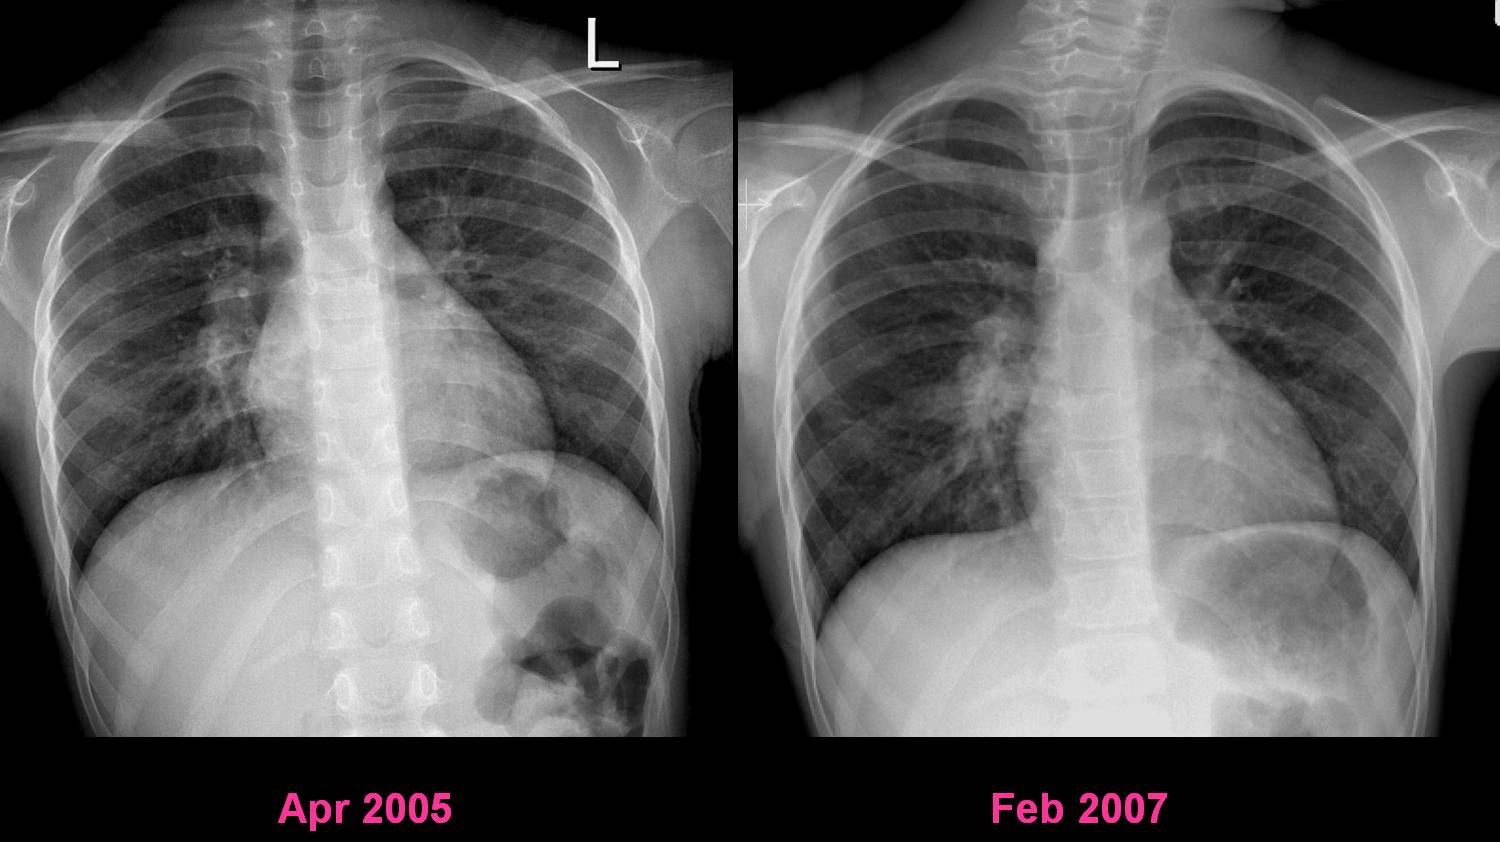

| Figure 2-a | Figure 2-b |